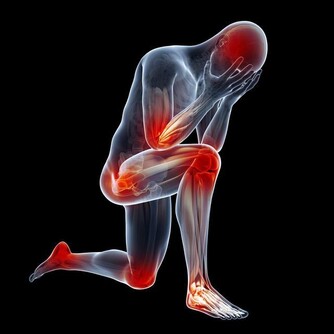

其中,缺乏維生素B1,容易引起消化不良、厭食、大便乾燥等症狀,嚴重的還會導致嘔吐、四肢浮腫等;

而缺乏維生素B6時,人的口唇、舌頭可能會有腫痛感,手指、腳趾還可能出現酥麻的刺痛感。